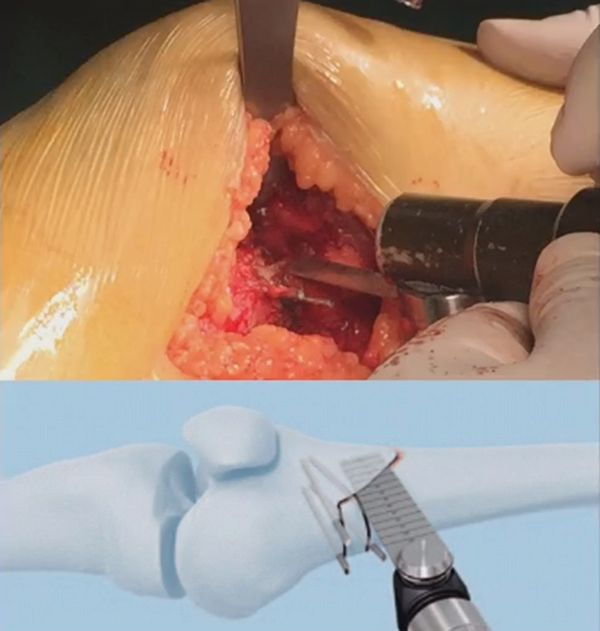

水平截骨时,同样放肢体中立位,后侧放一把骨撬保护后方重要结构。

截骨过程中,不要求一次截骨到位,把合页深度全部截到,可以留最后一点,用钻头由前向后打出一排筛孔来,把合页端弱化,再去做闭合时就不容易折断了。